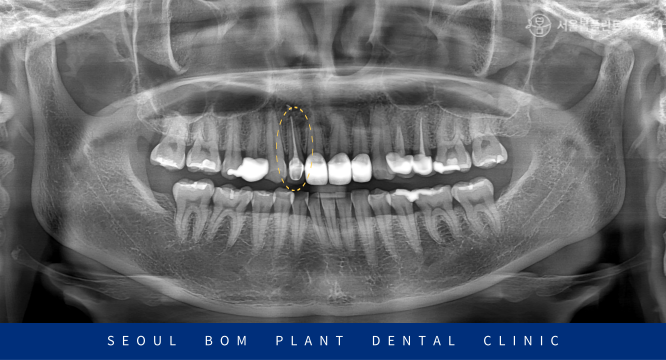

방이동치과 서울봄플란트치과에서는

눈에 보이지 않는 곳까지 확인하고

정밀한 검사를 위해

파노라마 사진을 촬영해 보았는데요.

다행히 기존 신경치료가 뿌리 끝까지

잘 되어 있었으며,

뿌리 끝 염증이나 통증 또한 없으셨습니다.

대개 이런 경우 의료진에 따라

발치를 해야 한다고 보는 경우가 많지만

환자분께서는 40대 초반의 젊은 나이셨습니다.

한 번 더 치아를 살려 사용하는 방법으로

치료를 진행하기로 계획을 수립하였습니다.

최종 보철물을 수복한 모습의

구강 내 사진과 파노라마 사진인데요.

자연스러운 색조와 형태로 크라운이 제작되어

수복한 치아가 어디인지 모를 정도로

심미적으로 개선된 것을 확인할 수 있었습니다.